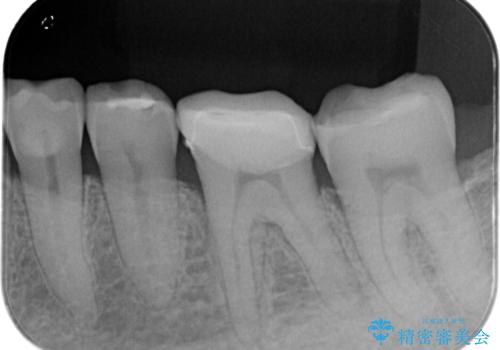

- 「噛むと歯が鈍く痛む」を主訴に来院されました。

よく見ると歯冠部に咬合面から近心側にのびるヒビ(クラックライン)が入っているのが見えます。

咬合力によるヒビの部分に生じる歪みを軽減するため、クラウンを被せました。

「噛むと歯が鈍く痛む」を主訴に来院されました。

各種検査を行い、咬合面にヒビ(クラック)を認めました。

元々咬合面にレジンインレーが入っており、近心歯質が薄くなっていたことや、食いしばるクセを持っていることも、ヒビが入った要因の一つと考えられます。

咬合力によるヒビの部分に生じる歪みを軽減するため、ヒビを追えるところまで切削しCR裏層・支台歯形成を行い、一度仮歯に置き換え症状の緩和を確認し、CAD/CAM冠を装着しました。